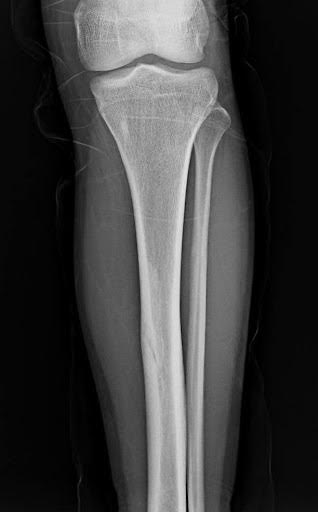

A 21-year-old female presents to the emergency room after falling from dancing on a table and injuring her right ankle. She is in severe pain and unable to bear weight comfortably with swelling and tenderness along the lateral malleolus. X-rays are taken and shown above.